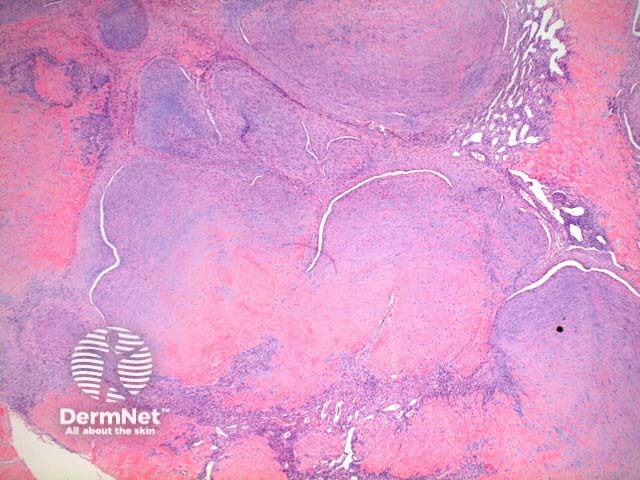

Low power view of myofibroma demonstrates a well defined multinodular tumour arising in the deep dermis or subcutis (Figure 1). Also at low power a branching ‘staghorn’ like pattern of blood vessels can be seen between the tumour nodules (Figure 2). Areas of calcification can often be seen (Figures 2, 3 and 5). The tumour nodules are comprised of a spindle cell proliferation with short plump nuclei (Figures 4,5 and 6). A basophilic tinge in the spindled peripheral component of the nodules is evident (Figures 7 and 8). Sclerotic collagen in the centre of the tumour nodules gives a biphasic appearance to the tumour (Figure 9).